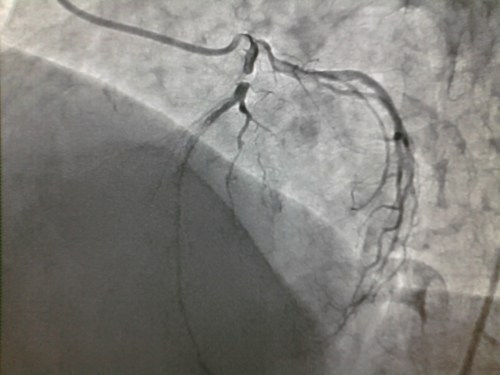

Thousands of coronary angiograms are done every day. Cardiologist no longer get excited to see exotic coronary lesions .Still , some images can be striking and dramatic. Here is an angiogram from a middle aged man with stable angina , who was one among the routine early morning diagnostic studies in our cath lab.

How this man was able to fill up the distal LAD almost completely? (With a complete cut off right in the neck of LAD )

Do you get any clue ?

- Can a trickle of ante grade flow sustain a TIMI 3 FLOW ?

- Or is it a very efficient instant collaterals from LCX ?

Yes . The first one is right . An almost invisible antegrade channel doing a exemplary job !